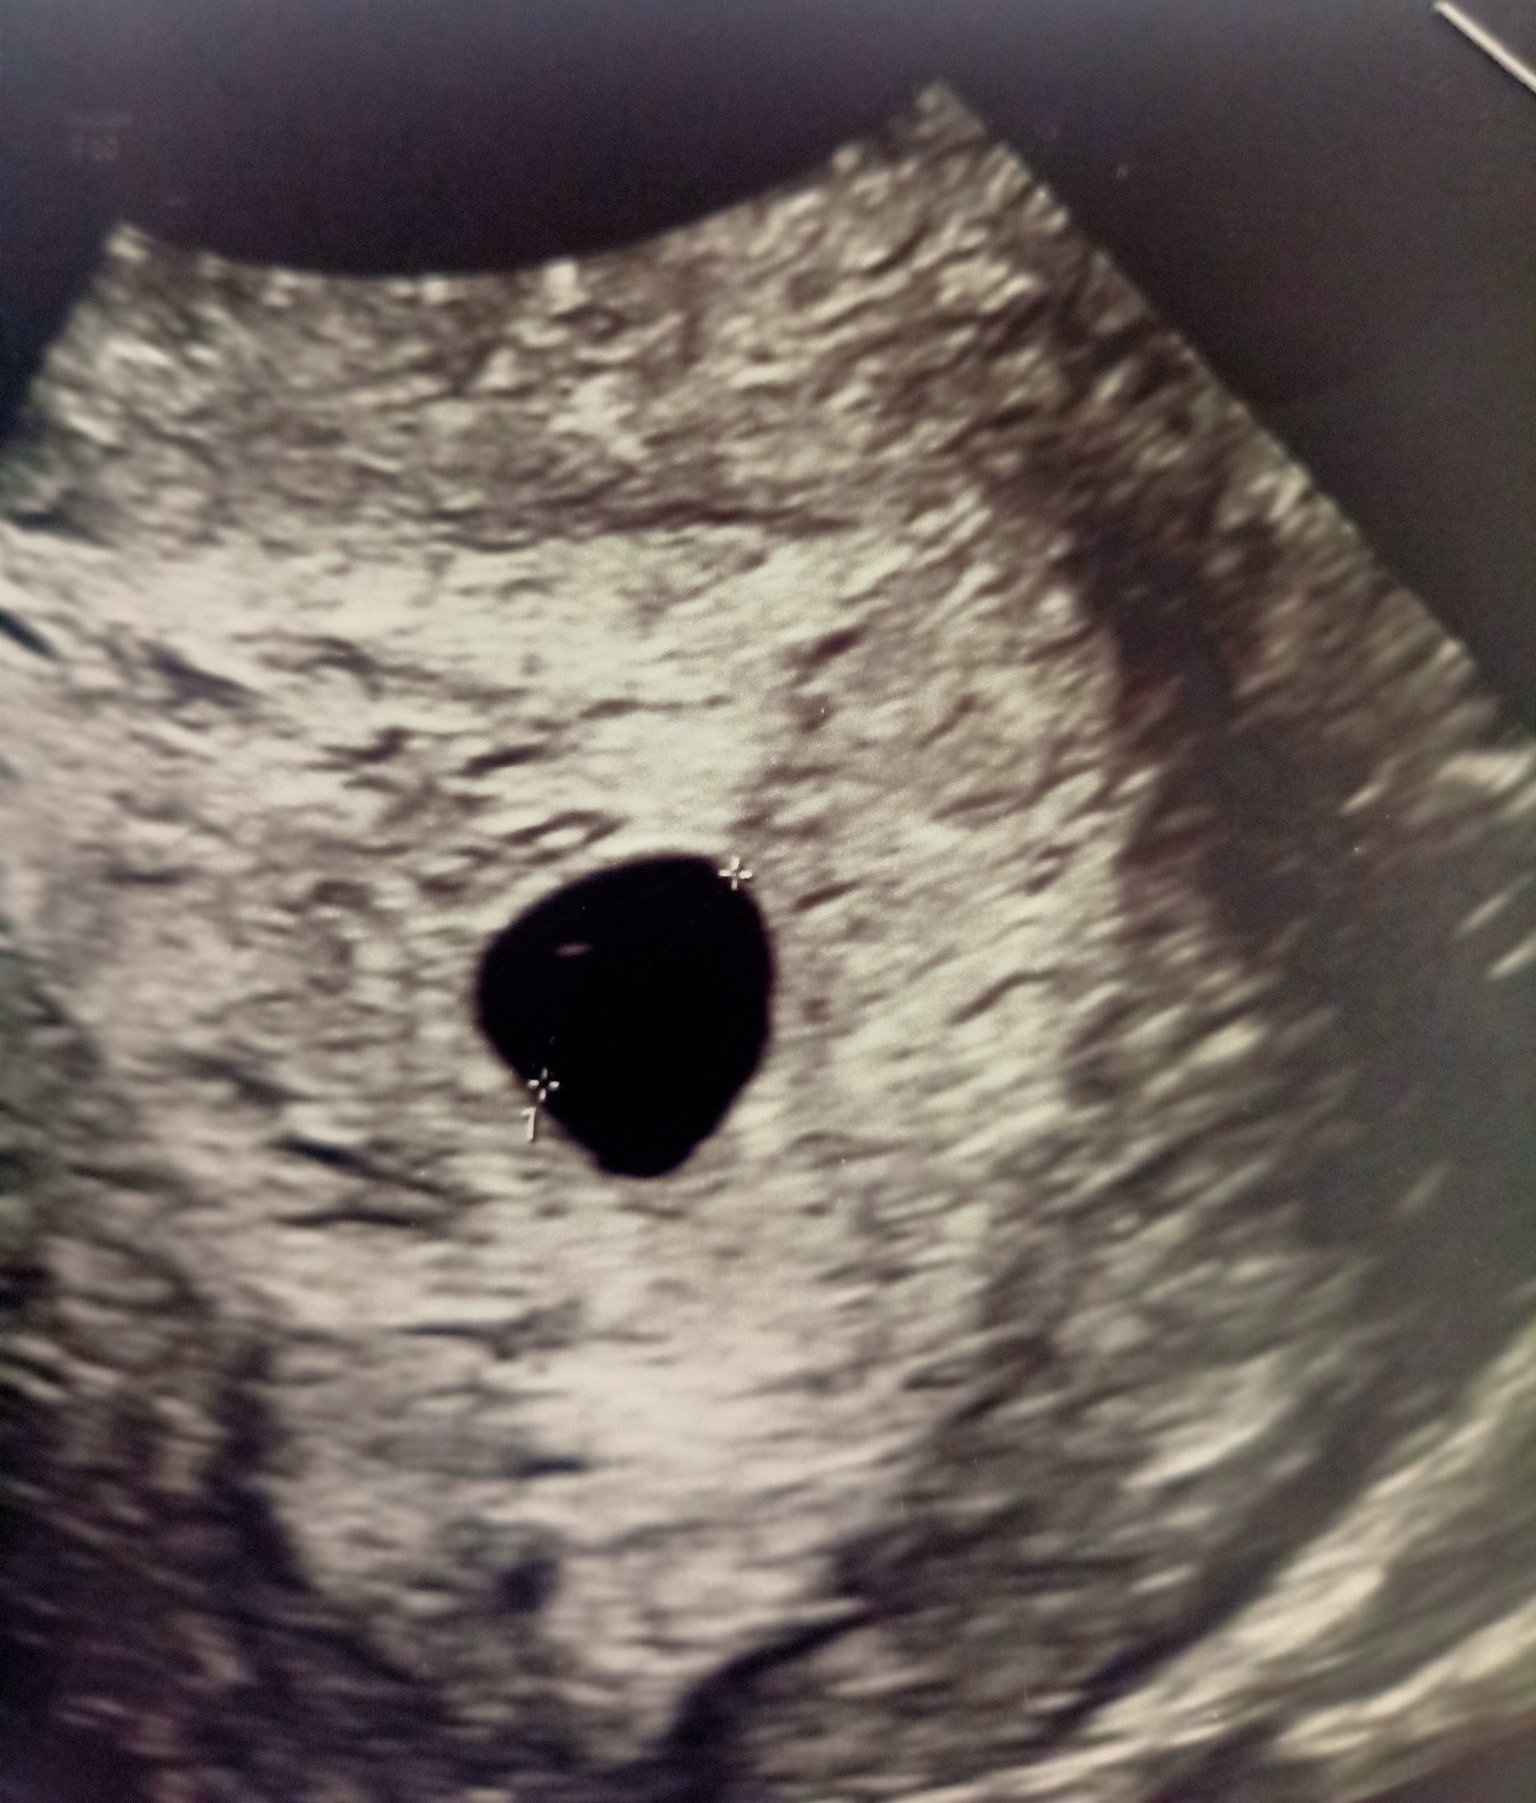

Здравейте не съм писала до сега днес бях на лекар каза че има плоден сак вие какво мислите

Прав е докторът,има плоден сак.Черната точка е сакът.

Благодаря  за отговора, според вас за 5 седмица добре ли е